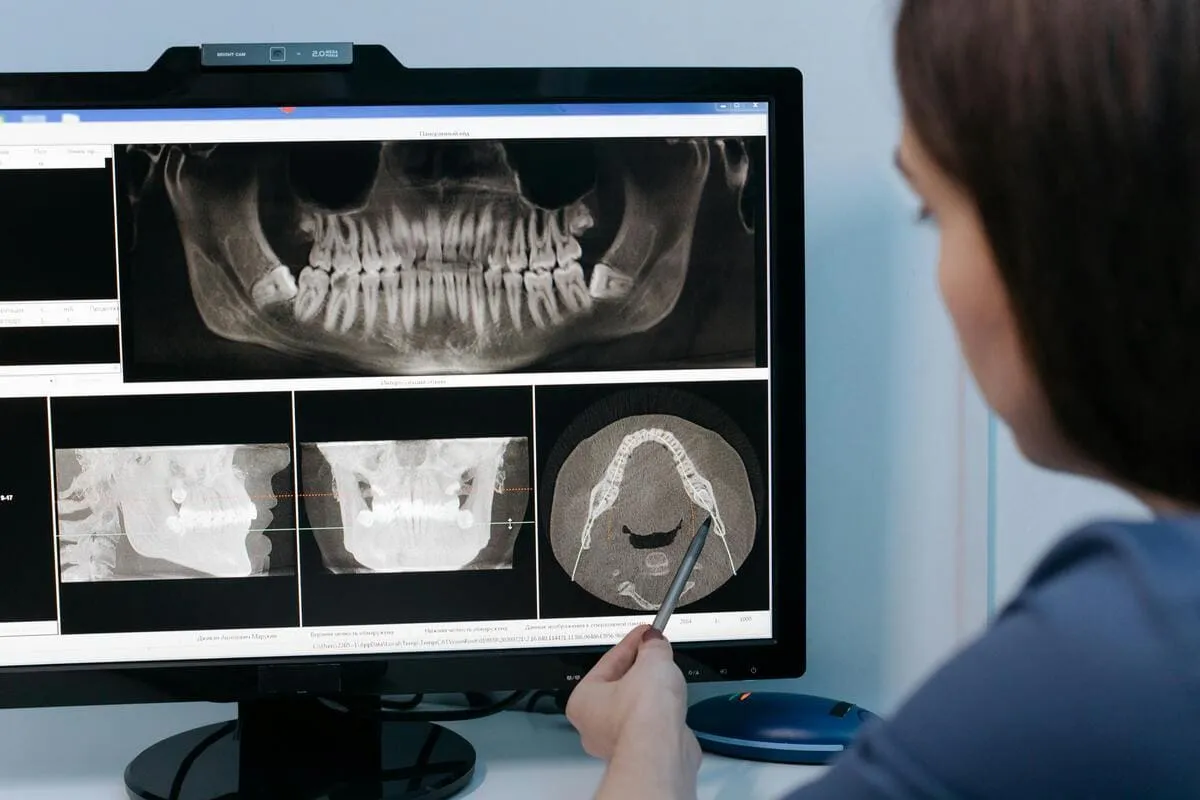

- Toma de tomografía dental

¿Debo realizarme una tomografía?

Si, una tomografía es indispensable al inicio de todo tratamiento con base en implantes dentales. Solo con ella se puede determinar el estado actual del paciente y planificar los implantes a instalar.